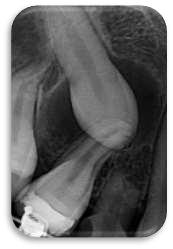

FIGURA 1 (TOMOGRAFIA VISTA FRONTAL)

Procedimiento:

Los caninos retenidos constituyen una anomalía eruptiva frecuente que requiere atención interdisciplinaria. El diagnóstico temprano mediante exploración clínica y radiográfica es esencial para prevenir complicaciones y planificar un tratamiento adecuado. La combinación de ortodoncia y cirugía representa la opción terapéutica más utilizada, con un pronóstico favorable si se actúa de manera oportuna